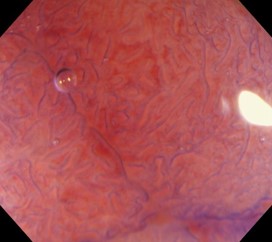

当院の大腸内視鏡検査では、100倍まで拡大可能な拡大内視鏡や、520倍まで拡大可能な超拡大内視鏡Endocytoを導入しています。特に520倍仕様の超拡大内視鏡Endocytoは、一般的には大学病院やがんセンターのみに導入されている特殊な機器で、クリニック規模の医療機関で導入されているのは、西日本では当クリニックのみとなります。

これら最新機器の導入により、迅速かつ高精度な診断が可能となっています。特に大腸内視鏡検査でポリープが発見された際には、非腫瘍・腺腫(良性腫瘍)・浸潤がん(悪性腫瘍)の鑑別やその深達度が重要となりますが、この拡大内視鏡・超拡大内視鏡を使用することで、これらの診断を即座に行うことができます。

確定診断はポリープ切除後の病理組織検査によって行いますが、超拡大内視鏡Endocytoは、病理診断で使う顕微鏡と同じ細胞レベルまでの拡大観察が可能で、病理診断とほぼ同じ精度の診断を行うことができ、ポリープ切除など検査時に必要な治療方針を即座に決定することができます。

- 12mmポリープ

- 拡大内視鏡(100倍)

- 超拡大内視鏡(520倍)